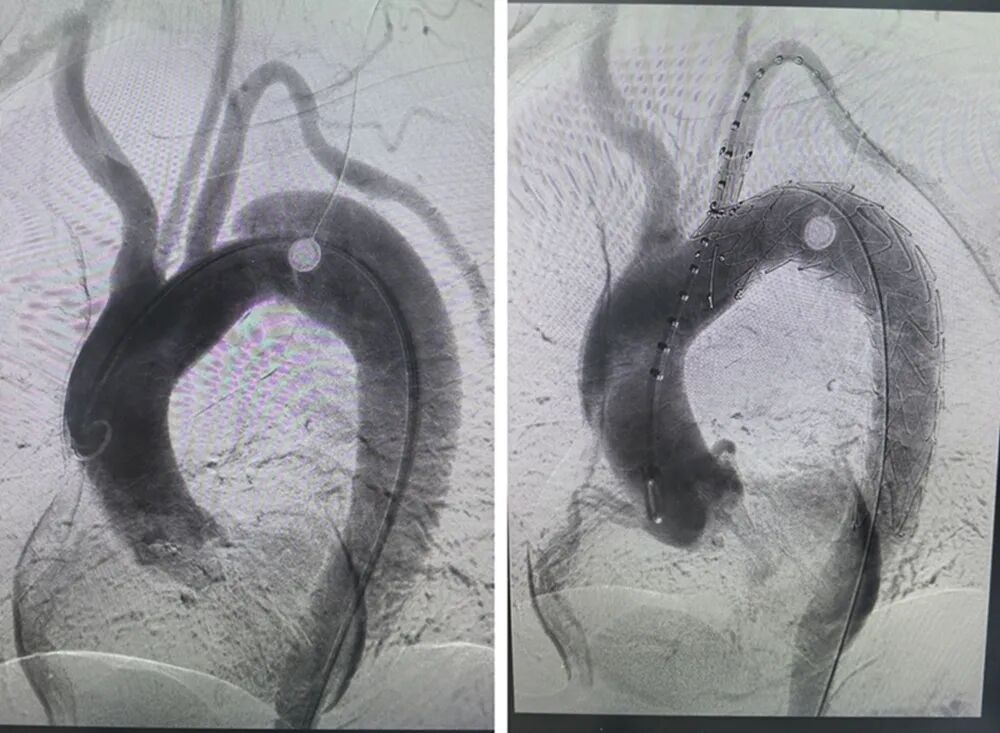

近日,霍邱县人民医院血管外科团队在安医大二附院血管外科专家的指导下,成功为一名复杂型主动脉夹层患者实施胸主动脉分支覆膜支架植入术。该例高难度手术的成功开展,不仅标志着霍邱县人民医院在主动脉急危重症救治领域迈上新台阶,也充分彰显了省级区域医疗(专科)中心建设带动下的优质医疗资源下沉实效。

患者王某某因“胸痛4小时”紧急入院,经急诊胸腹主动脉CTA检查,确诊为Stanford B型胸腹主动脉夹层,且夹层病变向上累及左锁骨下动脉开口,解剖结构复杂,手术操作难度极大。

主动脉夹层起病急骤、病死率高,被医学界公认为人体内的“血管炸弹”。为确保患者安全并实现精准修复,霍邱县人民医院血管外科团队迅速启动应急机制,与驻院帮扶的安医大二附院血管外科专家进行会诊,共同研讨手术方案。在孔令尚副主任医师的现场指导下,团队决定采用分体式心脉Cast支架系统,并运用单开窗技术,既实现了对主动脉夹层原发破口的有效隔绝,又精准重建了左锁骨下动脉血流,最大限度地保留了患者上肢及后颅脑的正常血供。手术过程顺利,术后患者生命体征平稳,恢复良好,目前已康复出院。